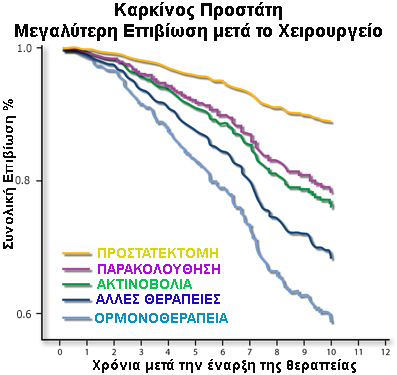

Σε κάθε θεραπεία καρκίνου ο πρωταρχικός σκοπός είναι η επιβίωση. Διάφορες μεγάλες μελέτες συμπεραίνουν ότι υπάρχει μεγαλύτερη πιθανότητα για μακροχρόνια επιβίωση σε ασθενείς που υποβάλλονται σε χειρουργείο σε σύγκριση με άλλες θεραπείες.

Σε μία μελέτη με 844 ασθενείς με εντοπισμένο καρκίνο του προστάτη, οι ασθενείς που υποβλήθηκαν σε προστατεκτομή είχαν υψηλότερα ποσοστά επιβίωσης από καρκίνο του προστάτη σε σύγκριση με τους άνδρες που επέλεξαν άλλες μορφές θεραπείας.2

Long-term survival probability in men with clinically localized prostate cancer treated either conservatively or with definitive treatment (radiotherapy or radical prostatectomy)

Objectives: To report the long-term survival probability in more than 3000 men with localized prostate cancer treated either conservatively or by definitive treatment (radiotherapy or radical prostatectomy).

Results: After adjusting for age, race, tumor grade, comorbid disease, income status, and year of diagnosis, the overall survival rate at 15 years was 35% for conservative management, 50% for radiotherapy, and 65% for radical prostatectomy. The corresponding prostate cancer-specific survival rates were 79%, 87%, and 92%. Patients undergoing radiotherapy or radical prostatectomy had lower overall mortality than patients undergoing conservative management (adjusted relative risk 0.67 for radiotherapy and 0.41 for prostatectomy; P <0.001). The increase in the survival duration was 4.6 years with radiotherapy and 8.6 years with radical prostatectomy.

Conclusions: The results of this study have shown that compared with conservative management, both radiotherapy and radical prostatectomy increase survival for men with localized prostate cancer.Κάντε κλικ ΕΔΩ για να κατεβάσετε ολόκληρο το άρθρο.